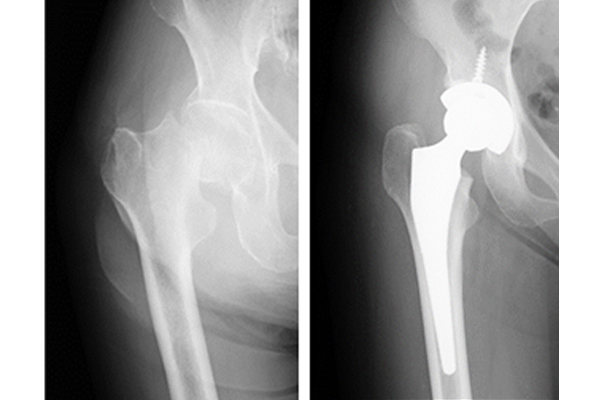

大腿骨頚部骨折は、血流が悪く骨癒合が得られにくい部位の骨折です。骨折部分の転位がある(ずれている)場合は、骨癒合が期待できないため、大腿骨頭を抜去し人工骨頭を挿入する手術を行います。患者さんの年齢や股関節の状況によっては人工関節置換術を行うこともあります。転位がない場合は、スクリューで固定する骨接合術を行います。

変形性股関節症

中高年の股関節の痛みの原因として変形性股関節症があります。多くは女性で、幼少期の発育性股関節形成不全が原因となっていることあります。初期の症状は立ち上がりや歩き初めに股関節に痛みが出現します。進行すると、股関節痛のため立ち仕事が困難となり日常生活にも支障をきたすことが多くなってきます。股関節部での変形が強い場合は、左右の足の長さの差が生じることもあります。レントゲンで診断することが可能です。場合によってはMRI検査を行うこともあります。

初期の場合は、リハビリテーションや鎮痛薬などの保存療法を行っていきます。症状も強く関節の変形がすすんでいる場合には、手術を行うことがあります。手術は主に人工関節手術を行います。

当院では人工関節手術にナビゲーションシステムを導入しております。ナビゲーションシステムとは、人工関節を設置する際に骨を削る角度や量を、赤外線とコンピューターで計測し、より精度の高い手術を行うシステムです。従来よりも正確性が高くなり人工関節が長持ちし、脱臼しにくいと考えられております。

手術翌日からリハビリテーションを開始し、2~4週程度で歩行可能となります。